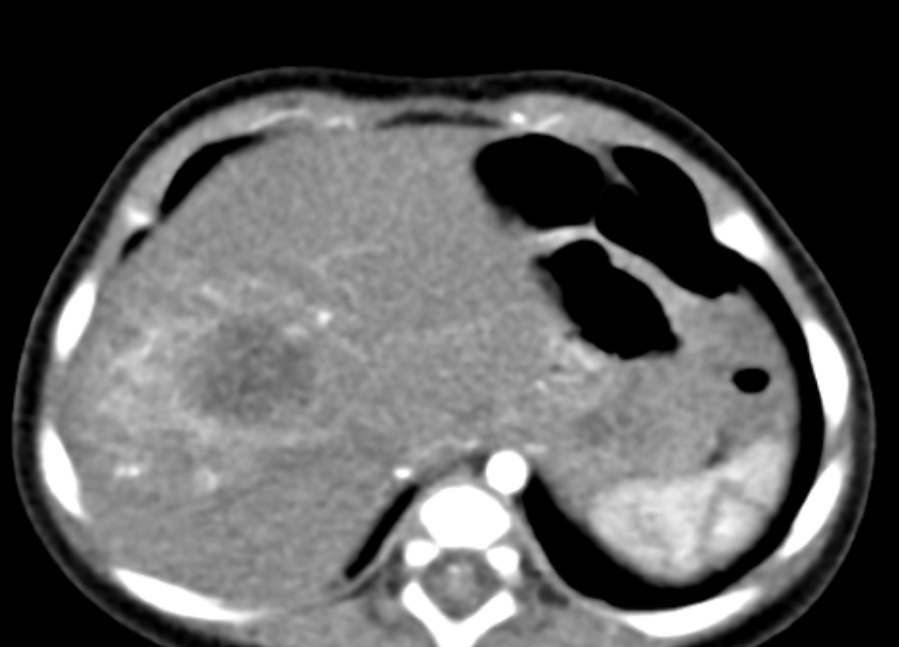

- Computed tomography

- Well defined mass with regular borders that is hypoattenuating in comparison with the adjacent hepatic parenchyma

- Common diffuse heterogeneous contrast enhancement

- Half of all hepatoblastomas appear lobulated or septated, especially on contrast enhanced images (Radiol Bras 2017;50:68)

Radiology images